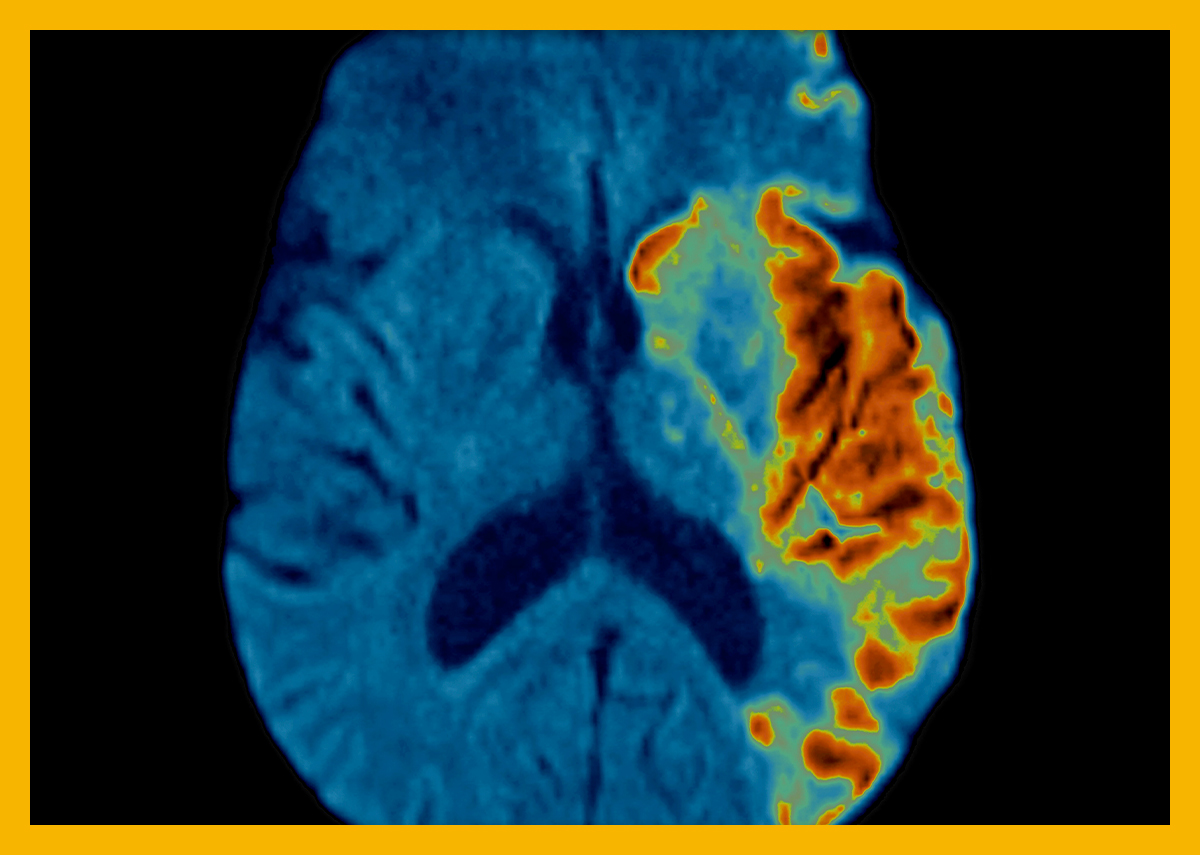

초기에 특별한 증상이 없으면 고혈압임을 알기 어려우므로 정기적으로 혈압을 측정하지 않으면 자신이 고혈압인지 모르고 무시하게 되어 합병증. 고혈압을 규칙적으로 관리해야 하는 이유는 이러한 합병증 때문입니다. 고혈압의 주요 원인은 고혈압이기 때문입니다. 무시하면 고혈압은 혈관이 견딜 수 있는 압력 수준을 넘어 혈관이 파열되거나 막히게 됩니다. 이 이론은 뇌경색, 뇌출혈 및 협심증과 같은 심각한 질병으로 이어질 수 있습니다. 이외에도 급성 심근경색 등의 다른 합병증도 유발할 수 있어 항상 주의를 기울여야 한다.